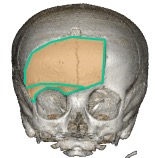

il existe plusieurs voie d’abord pour les tumeurs supra-sellaires.

la voie sous-frontale est la mieux adaptée pour aborder la région supra-sellaire dans un but d’exérèse car elle permet le contrôle de la ligne médiane. la dépose du bandeau orbitaire aide grandement pour éviter de rétracter le cerveau de façon excessive et de contrôler la face inférieure du chiasma. cette voie permet la préservation de la bandelette olfactive contre-latérale et parfois également homolatérale.

l’ouverture de la lame terminale permet d’accéder au contenu du V3 et de le faire descendre sous le chiasma (cf. ci-contre).